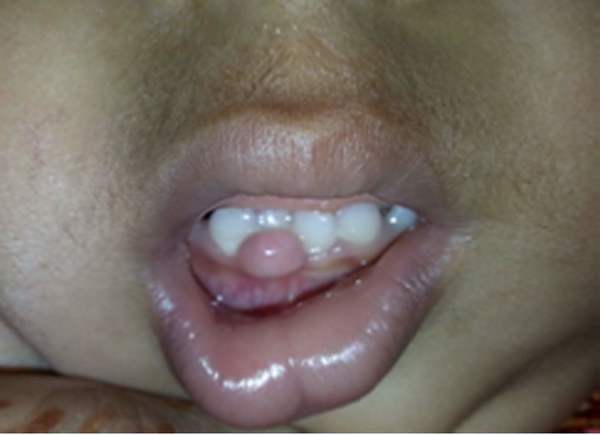

Ювенильный тип – заболевание у подростков

Такой тип , еще он называется – юношеский гингивит, встречается у детей от 7 до 12 лет, а также у девочек от 12 до 16 лет и у мальчиков с 13 до 18 лет.

Проявляется заболевание в разрастании тканей краёв десны, при этом появляются каплеобразные выступающие десневые сосочки

С возрастом проявление симптомов заболевания снижается. Так как происходит изменение гормонального фона, а также так как уход за полостью рта становится более тщательным.